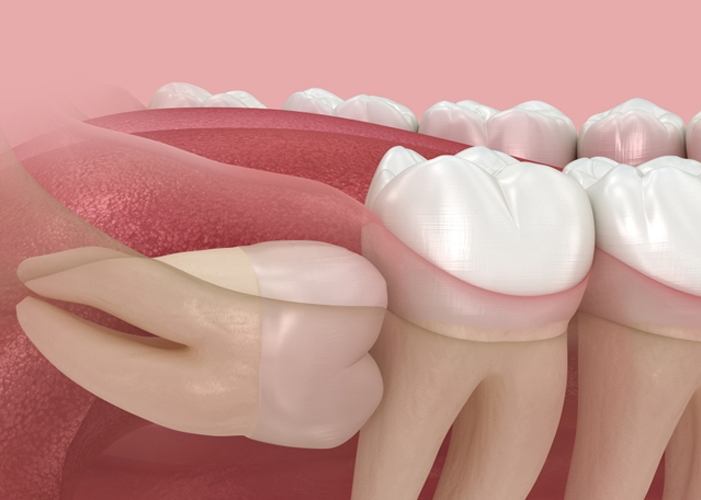

05

하루만에 발치 후 바로 식립하는발치즉시 임플란트

발치한 당일에 임플란트 식립을 진행하기 때문에

내원 횟수를 줄여 불편함을 최소화하고 치료 기간도 단축시킬 수 있습니다.

다만, 모든 분들이 가능한 것은 아니기 때문에 정밀 진단 후

숙련된 의료진과의 상담이 필요합니다.

사랑니 발치 PROCESS